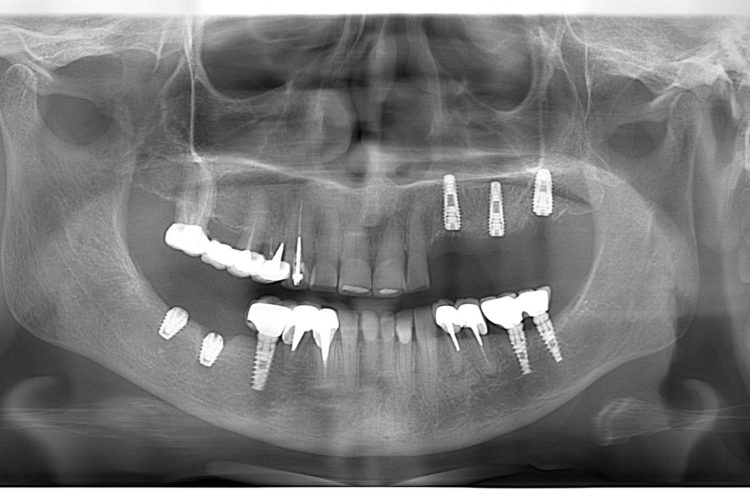

Pacienta in varsta de 74 ani s-a prezentat in clinica pentru reabilitare orala complexa si estetica. Planul de tratament a inclus implanturi Dentium, lucrari insurubate pe implanturi, fatete si coroane din hibrid